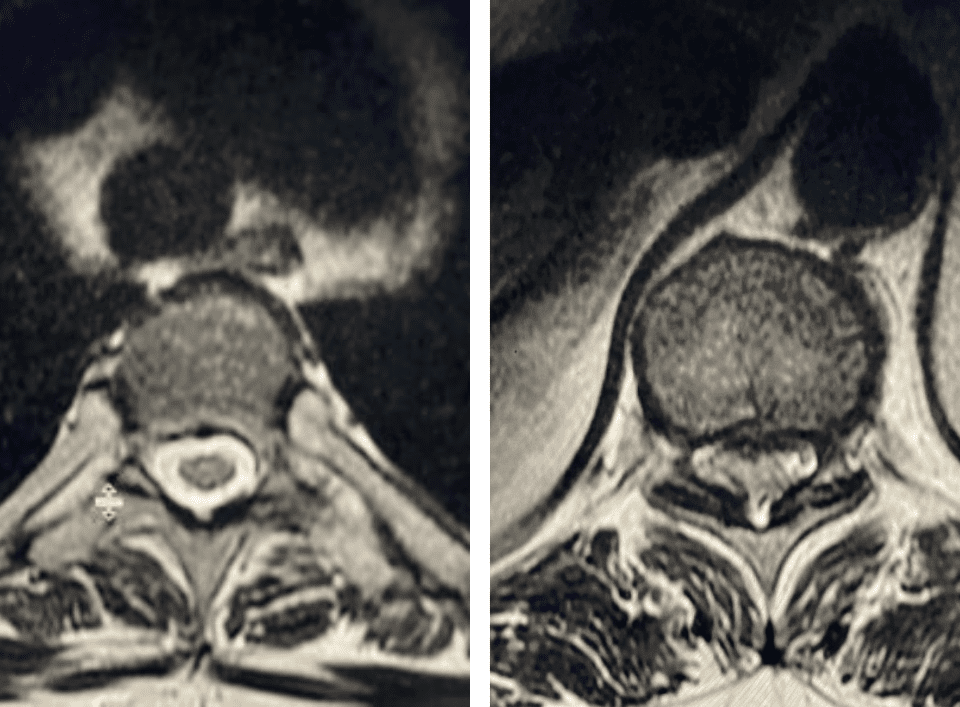

Nervous tissue is soft. The thecal sac is surrounded by a rigid bony ring which forms the spinal canal. Any mass that fills the very small […]